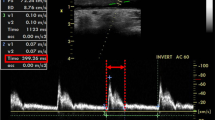

All patients were clinically assessed by a blinded ICU consultant. Only patients being supposed to be volume demanding [based on clinical signs of inadequate tissue perfusion (e.g., escalating vasopressor requirement, decreasing urine output, etc.)] were included into the observation. At the ICU, patients were sedated using propofol and sufentanil and controlled mechanically ventilated [airway pressure release ventilation (APRV), VT 8 ml/kg BW, Ppeak ≤ 25 cm H2O, 10 cm H2O ≤ positive end-expiratory pressure (PEEP) ≤ 13 cm H2O, average I:E ratio 1:1.5 (individual titration to ensure complete expiration and avoid intrinsic PEEP), SaO2 ≥ 95 %, PaCO2 ≤ 45 mmHg]. Sonographic measurement of the CCA was performed using a Philips HD15 ultrasound device (Philips Healthcare, Hamburg, Germany), equipped with a linear transducer (L12-3 Broadband Linear Array Transducer, Philips Healthcare). By default, patients arriving at the ICU after cardiac surgery had received a central venous catheter preoperatively, usually inserted into the right internal jugular vein. To avoid any risk of infection at the puncture site, sonographic measurements were conducted on the contralateral side only, usually on the left. All sonographic images were obtained by two board-certified anesthesiologists, each with experience of more than 100 ultrasound-guided central venous cannulations. The hemodynamic data were collected by another investigator, blinded for the results of sonography. Ultrasound examinations and collection of hemodynamic data were performed with the patient in supine position with the head of bed 30° elevated (semi-recumbent). CCA was visualized by placing the ultrasound transducer perpendicular to the skin in a transverse plane on the patient’s neck lateral to the cricoid cartilage (short axis view). The artery was identified by compression as well as by color Doppler imaging. To avoid any influence of external compression on the CCA diameter during the following examination, sufficient ultrasound gel was used to allow the transducer to lose direct skin contact, thus applying the least possible amount of pressure. A B-Mode scan was recorded simultaneously with the electrocardiogram, the image was frozen at end-expiration, and the diastolic antero-posterior diameter of the CCA was measured in centimeters from intimal to intimal edge within the frozen B-Mode image. The procedure was repeated two times, and the mean diastolic CCA diameter was calculated from these three measurements. Thereupon, the transducer was removed and its location was marked on the skin.

CCA was visible and easily identifiable in all patients. The percentage CV values, revealing high intra- as well as inter-observer reliability, were as follows: assessment 1: 12.93; assessment 2: 14.37; observer 1: 14.4; observer 2: 12.91. Median diastolic CCA diameter measured from intima to intima was 6.2 (5.4–7.1) mm prior to volume expansion (Fig. 1). Hemodynamic assessment revealed median values for MAP and PPV of 68 (60–73) mmHg and 17.6 (16.8–23.9) %, respectively. Immediately following administration of a bolus of crystalloid infusion solution (7 ml/kg BW), sonography was repeated and revealed a significant increase in median diastolic CCA diameter to 6.7 (5.8–7.3) mm (p = 0.03). Overall CCA diameters increased by 5.0 (1.9–10.5) % in comparison to the arterial diameters measured prior to fluid bolus in all patients. MAP likewise increased upon expansion of intravascular volume [85 (71–100) mmHg, p < 0.001], whereas PPV was significantly reduced to 13.2 (6.7–18.1) % (p < 0.001).

Effect of intravascular volume expansion on CCA geometry, MAP and PPV. CCA diameter increases with intravenous administration of crystalloid infusion solution (7 ml/kg BW) (left). MAP increases with intravenous administration of infusion solution (middle). PPV is reduced upon intravenous administration of fluid (right). CCA common carotid artery, MAP mean arterial pressure, PPV pulse pressure variation. Data are given as median with percentile 25–75. Wilcoxon matched pairs test, *p < 0.05; ***p < 0.001. n = 20

We administered a standardized bolus of crystalloid infusion solution within about 15 min and noted a subsequent significant increase of CCA diameter measured during cardiac diastole (Fig. 1). This corresponds to what Marik et al. described when using carotid artery Doppler ultrasound to assess hemodynamically unstable patients (Marik et al. 2013). In that study, a passive leg raising (PLR) maneuver, used as a temporary and reversible volume loading, induced an 80 % increase in carotid blood flow. Interestingly, similar to our observation, the simultaneously assessed diameter of the CCA likewise increased in that study. However, according to the formula “flow rate = ¼ × π × diameter2 × velocity”, an, e.g., 20 % increase in diameter contributes to more than the half of the increase in carotid blood flow (Nocke et al. 2014).